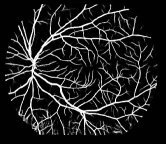

Refer to caption

Figure 4: An illustration of short connections. We use four groups of convolution for VGGNet and ResNet-101.

Figure 5: (a) Bottom-top short connection between feat_conv1 and feat_conv2 (b)top-bottom short connection between feat_conv4 and feat_conv1

We adopted bottom-top short connections to deliver detail information just as shown in Figure 4. There are three bottom-top short connections in total. Suppose we use VGGNet as backbone. We can observe from Figure 4 that there are four groups of convolution (conv1, conv2, conv3 and conv4) for feature learning in total. We first convolved the last convolution of each group using 16 convolution kernels with size 1×\times1. Then, the obtained feature maps are up-sampled 1×\times, 2×\times, 4×\times, 8×\times respectively to restore to original resolution. Bottom-top short connections are among feat_conv1, feat_conv2, feat_conv3, and feat_conv4.

Let’s take bottom-top short connection between feat_conv1 and feat_conv2 as an example (see Figure 5). The information (feat_1_2) passed from feat_conv1 is concatenated with feat_conv2 to get feat_conv2_fuse. Then, one hand hand, we perform a 1×\times1 convolution operation on feat_conv2_fuse to get the information (feat_2_3) delivered to feat_conv3. On the other hand, we performed convolution operation with a kernel size of 1×\times1 and sigmoid transformation for feat_conv2_fuse sequentially to obtain the segmentation result (side 2). At last, side 2 is compared with the ground truth to get the loss of the second side-output layer.

2.3 Top-bottom short connection

Bottom-top short connections aim to refine high-level segmentation results. However, we can observe from the first two rows in Figure 1 that the vessel map generated by the first side-output layer contains too many noises while the map generated by the last side-output could capture the main vessel structure. Therefore, we propose delivering high-level structural information to the first side-output layer to reduce its noises. We implemented this kind of information delivery by a top-bottom short connection from conv4 to feat_conv1, which can been seen in Figure 4. We first convolved the last convolution of conv4 using 1 convolution kernels with size 3×\times3. Then the obtained feature map are up-sampled 8×\times to get feat_4_1. The information (feat_4_1) passed from conv4 are concatenated with feat_conv1 to form feat_conv1_fuse (see Figure 5). At last, one hand hand, we perform a 1×\times1 convolution operation on feat_conv1_fuse to get the information (feat_1_2) delivered to feat_conv2. On the other hand, we performed convolution operation with a kernel size of 1×\times1 and sigmoid transformation for feat_conv1_fuse sequentially to obtain the segmentation result (side 1). At last, side 1 is compared with the ground truth to get the loss of the first side-output layer.